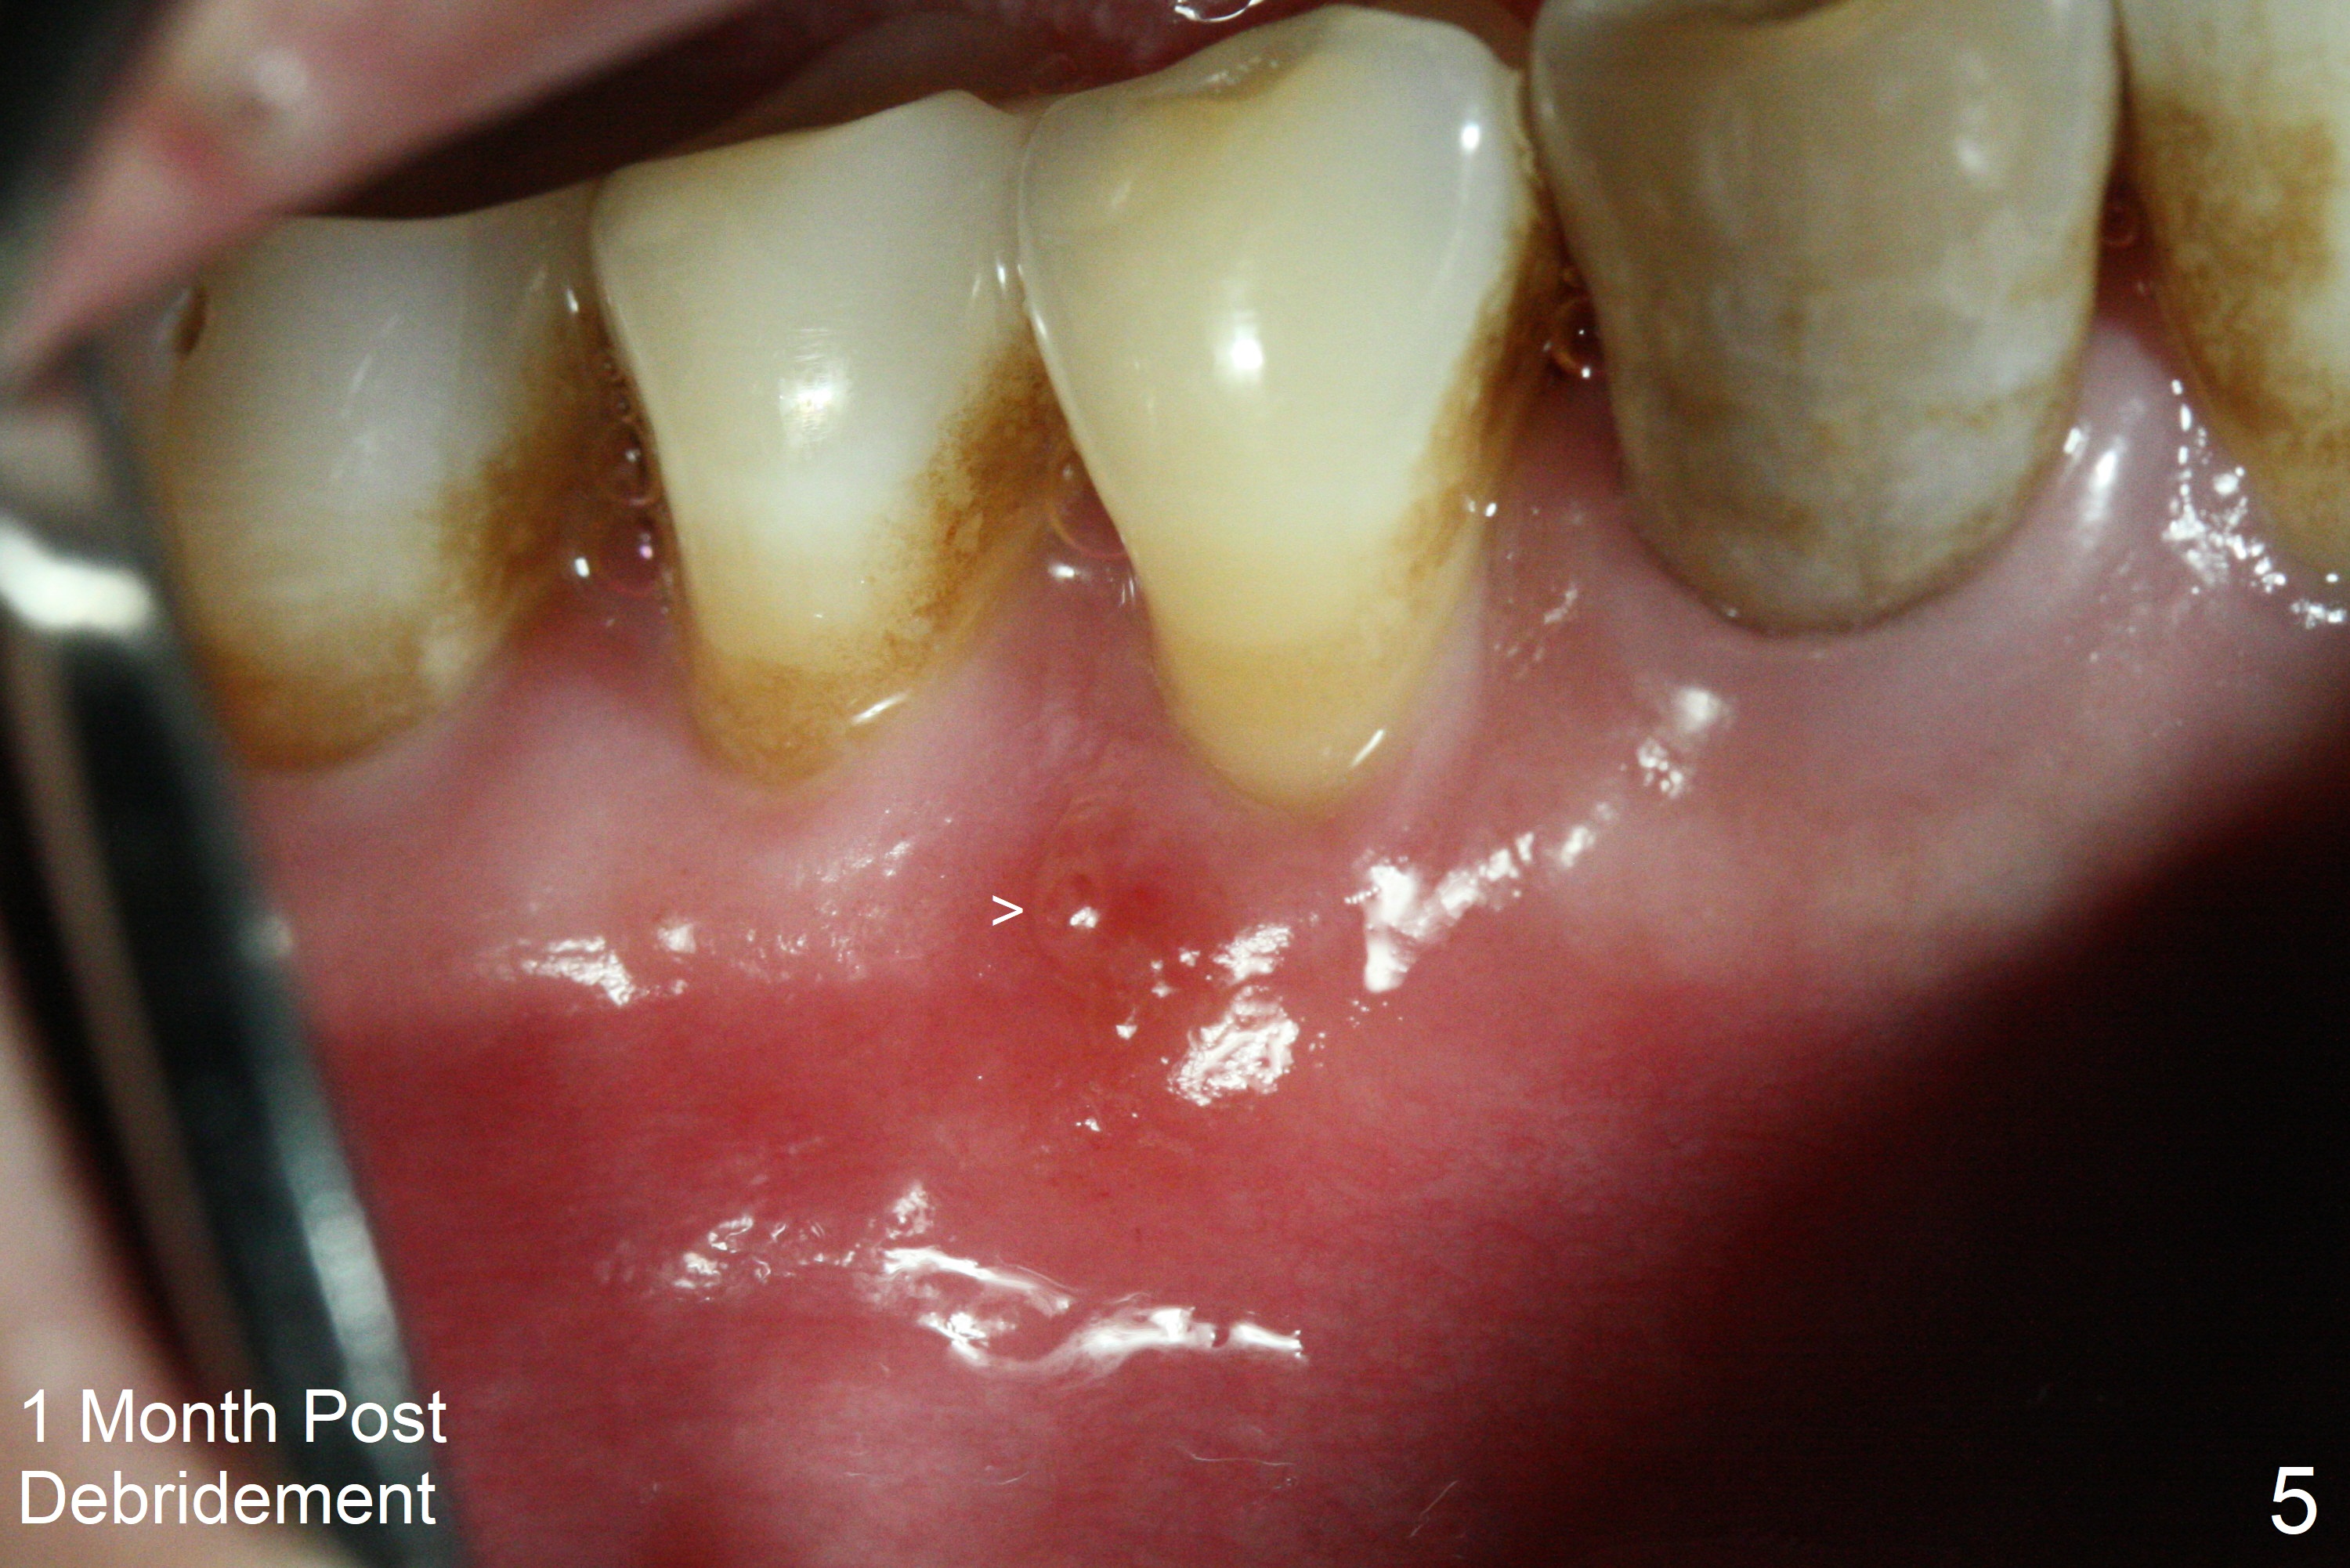

The patient reports that the fistula disappears after initial RCT at #27, but it seems to re-appear 1 month post canal debridement (Fig.5 >). After repeated debridement with #40 hand file at 23 mm, apply Endo Sequence BioCeramic Sealer and insert GT 40/.08 master cone with black carrier (Fig.6). One hour later, the patient returns with re-appearance of the fistula (Fig.7). Following local anesthesia, poking the fistula leads to sealer escape (Fig.8). After debridement of the fistula until the bone, PA is retaken (Fig.9). A crown was made in China; mesial radiolucency starts (Fig.10). The tooth remains asymptomatic 1 year 5 months postop (Fig.11). There is a lingual fistula with enlarged mesial radiolucency 2 years 3 months postop (Fig.12-14).